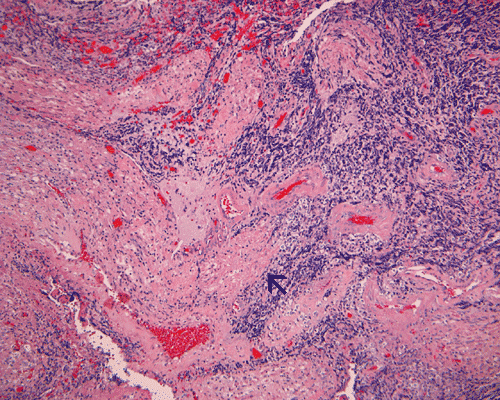

Pathology of the case:

The surgery removed several irregular fragments of tan, soft tissue for examination that were 2.5 x 1.2 x 1.0 cm in toto. Histologically, the lesion is a highly cellular neoplasm with tumor cells packed in solid sheets and without a specific architectural pattern (Panel D). Small, focal necrosis is also present (not shown). The tumor has rich vascularity and the endothelial cells seem to be active (Panel E). Almost all the tumor cells have only a thin rim of amphophilic cytoplasm, large nuclei with prominent nucleoli (Panel E and F). Clear cytoplasm is present in some tumor cells. In general, the cells do not look epithelioid or spindle. In some of the tissue fragment, the tumor shows invasion into the peripheral nerve root with dissection of the nerve fibers (Ú in Panel G and H). This phenomenon is well demonstrated by reticulin stain (Panel I) and immunohistochemistry for neurofilament proteins (Panel J). About half of the tumor cells are strongly positive for vimentin (Panel K). There is also scant positive tumor cells for S100 protein (Panel L) and cytokeratin AE1/3 (Panel M). The tumor cells are negative for neuorfilament proteins (Panel K) and smooth muscle protein (Panel N).